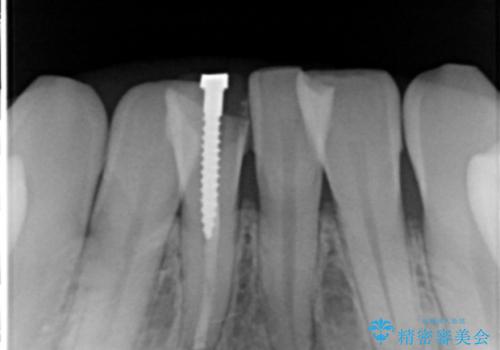

- 下の前歯の色が気になることを主訴に来院された患者様です。

下の前歯は金属の土台により黒くなり、隣の歯も神経が死んで暗く変色していました。

神経が死んでいる歯の根管治療を行った後、セラミッククラウンによる補綴治療を行いました。

※右下1の再根管治療もおすすめしましたがご希望されませんでした。